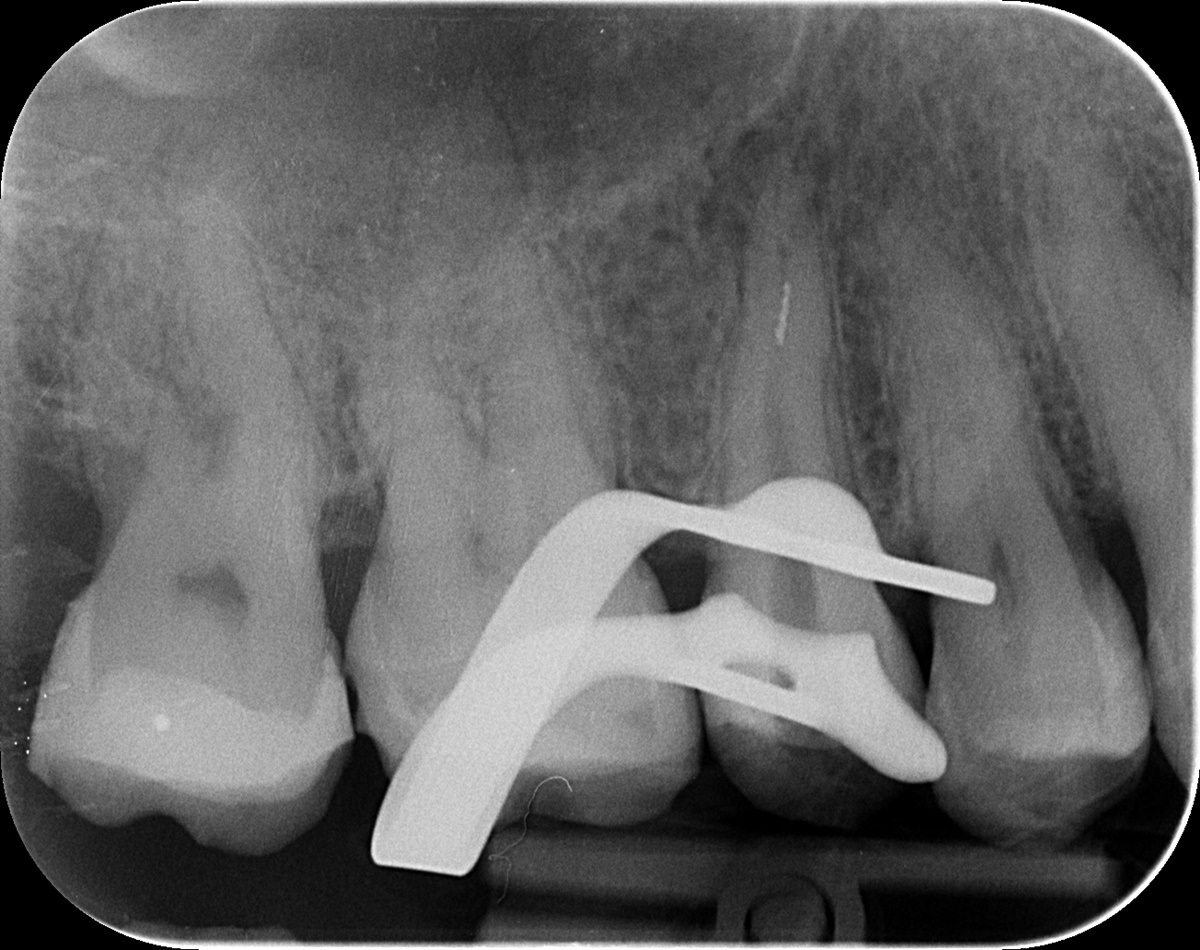

Az érintett jobb felső ötös fogról a páciens már egy kis fogfelvétellel érkezett. A kezelés megkezdése előtt a röntgen megtekintésekor feltűnt, hogy valószínűleg nem egy, hanem két betört fragmentumról van szó. Ezek a fogak gyakran két csatornával rendelkeznek, illetve ebben az esetben egy érdekes variációval: a két csatornának közös vége van. Ilyenkor az egymás felé ívelő gyökércsatornák meglehetősen görbék lehetnek - tipikus helyei a tűtöréseknek.

Először a szájpadlás felőli gyökércsatornában tártuk fel a tűt. Óvatosan, a megfelelő technikát alkalmazva sikerült eltávolítani a kb. 4 mm-es darabot. Ilyenkor készítünk egy kontrollröntgent, hogy lássuk, valóban nem maradt bent semmi az eltávolított tűből. Ekkor vált biztossá a gyanúnk, van még egy műszer a fogban.